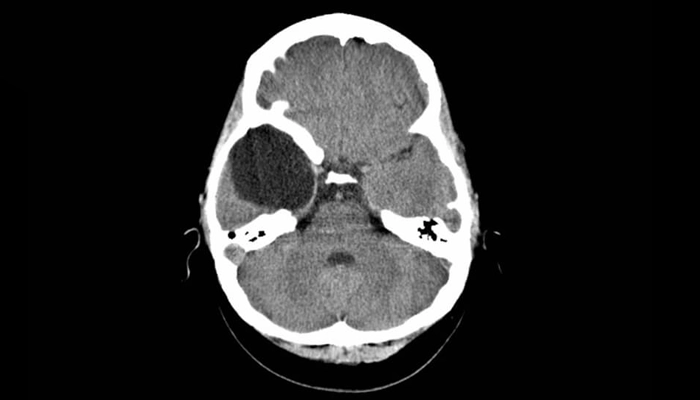

Chụp cắt lớp vi tính (CT scan): Giúp phát hiện nhanh u nang, đặc biệt hữu ích trong cấp cứu hoặc khi không thể thực hiện MRI.

U nang màng nhện (Arachnoid cyst) là những túi chứa dịch não tủy hình thành trong lớp màng nhện – một trong ba lớp màng bao bọc não và tủy sống. Các nang này thường có tính chất bẩm sinh, vách mỏng và chứa dịch trong suốt có thành phần tương tự dịch não tủy bình thường.

U nang màng nhện thường được phát hiện tình cờ qua các phương pháp chẩn đoán hình ảnh như CT hoặc MRI, và có thể khiến người bệnh lo lắng dù đa số trường hợp là lành tính. Tuy nhiên, do nằm trong không gian nội sọ kín, sự tồn tại hoặc phát triển của nang vẫn cần được theo dõi định kỳ để tránh nguy cơ chèn ép cấu trúc não. Hiểu rõ bản chất bệnh lý giúp người bệnh tiếp cận vấn đề một cách khoa học và giảm bớt lo lắng không cần thiết.